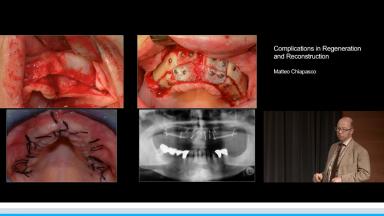

Complications in Regeneration and Reconstruction

This lecture reviews in detail the various defects encountered in clinical practice that may need regenerative procedures for hard and soft tissue augmentation. The presentation is supported with excellent visual aids that illustrate how these defects can be reconstructed for prosthodontically driven implant placement. It also addresses how to prevent complications in regenerative and reconstruction procedures as well as the predominant treatment options to manage these complications. Clinical outcomes are supported by reference to several studies and clinical recommendations from the 4th ITI Consensus Conference.

- describe the various bone defects encountered in clinical practice to be considered before implant placement

- discuss how to prevent complications related to bone augmentation procedures

- discuss the predominant treatment options for management of complications associated with reconstructive procedures

- explain therapeutic interventions to manage complications at different stages of implant therapy